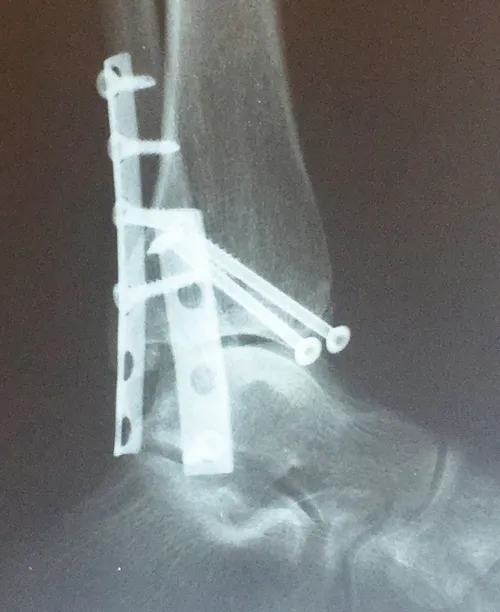

Xray and CT scan of displaced medial and posterior malleolar fracture with ORIF

Preop and Postop ORIF Posterior Malleolus Fracture with associated Fibular fracture

Preop and Postop Trimalleolar Fracture with Fixation of Posterior Malleolus Fracture

Preop

Postop